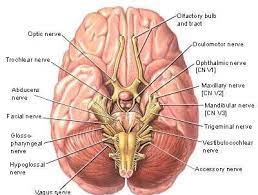

قیمت: 69٬000 تومان - دسته بندی فایل: پاورپوینتپاورپوینت بررسی مغز و اعصاب

فروش ویژه پاورپوینت حرفه ای بررسی مغز و اعصاب / تعداد اسلاید: 73 اسلاید

قیمت: 59٬000 تومان - دسته بندی فایل: پاورپوینتپاورپوینت بررسی اعصاب جمجه ای

فروش ویژه پاورپوینت حرفه ای بررسی اعصاب جمجه ای / تعداد اسلاید: 43 اسلاید